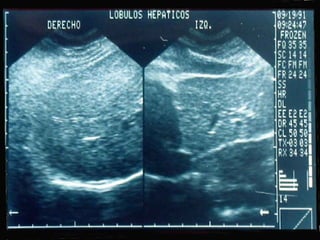

SONOGRAMA ABDOMINAL EVALUACIÓN TAMAÑO ( Hepatitis, I.C.C., Cirosis) FORMA (lobular en cirrosis) LOCALIZACIÓN ( de masas) PATRON SONOGRÁFICO ( hiperecoico gris)

SONOGRAMA ABDOMINAL EVALUACIÓN HIGADO SISTEMA BILIAR BAZO  RIÑONES PANCREAS ( no específico)